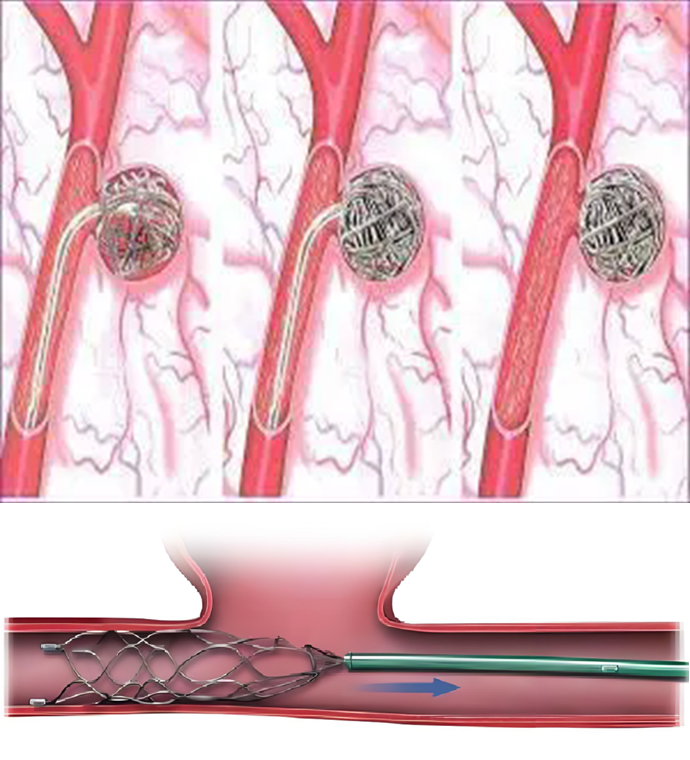

栓塞:通过导管将栓塞材料送至瘤体内,阻断瘤体血供,使瘤体逐渐变小。难度相对较大,花费较大

支架置入:对于瘤体较大或伴有动脉狭窄的患者,可考虑支架置入,以重建动脉血流通道。

一般用于距离股总动脉分叉1cm以上的假性动脉瘤。